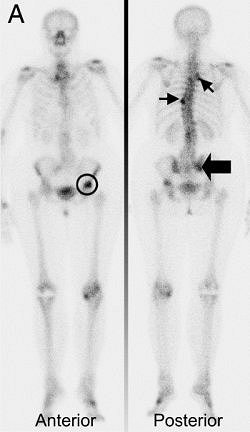

![]() |

| Seventy-four-year-old woman, under tamoxifen treatment, presented with positive bone scan showing multiple lesions in vertebral spine T3 and ribs, T9 (small arrows), right sacroiliac region (thick arrow), and left femur (circle). |